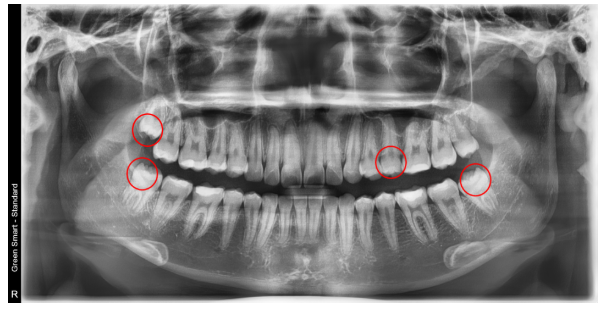

상악 좌측 제2 소구치 발치

상악 우측 & 하악 양측 사랑니 발치

교정용 미니스크류를 이용하여 치아 후방 이동

발치: 상악 좌측 제2 소구치, 상악 우측·하악 양측 사랑니